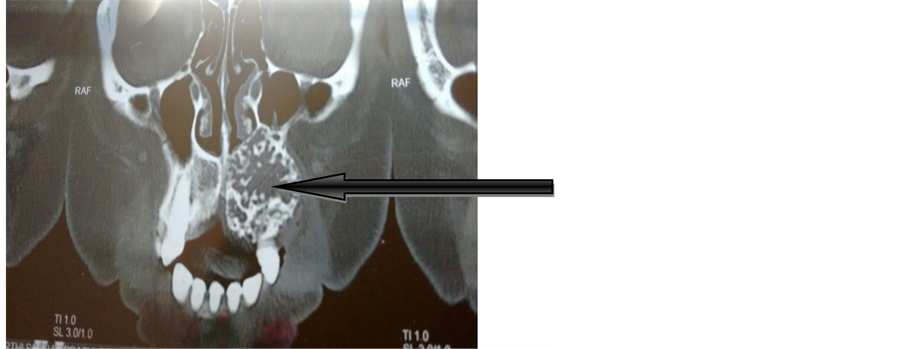

A 47-year-old female, with non-contributory cultural, social, and medical histories, presented to the out-patient department of otorhinolaryngology, Government Thanjavur Medical College, Thanjavur, Tamilnadu, India. Patient had a history of swelling in the left upper jaw for more than 7 years; it was slow growing and painless. On clinical examination 5 × 5 cm smooth swelling seen on the left premolar area (Figure 1). It was hard in consistency, which was painless and uneventful. Teeth 21, 22, 23, 24 and 25 were immobile; there is no displacement of the roots of teeth observed. Coronal view of CT Para nasal sinus revealed a poorly defined, mixed, radiolucent-radiopaque image, suggesting a benign fibro-osseous lesion (Figure 2). No cervical lymph node was palpable. Patient was subjected to incisional biopsy and it was approached by sublabial incision. Small piece about 1 cm removed from the swelling by gauge and mallet and sent for histopathological examination and it was reported as desmoplastic amelo- blastoma.

Figure 2. CT PNS.